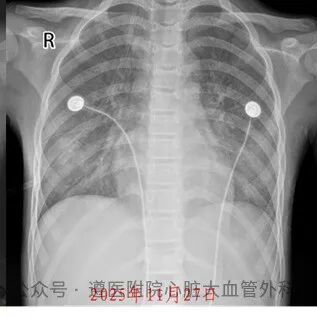

转运成功只是开始。严重低氧和低血压已导致患儿多器官功能衰竭,深度昏迷,瞳孔反射迟钝;心肌严重受损,心脏功能极差;肺部几乎完全失去功能,胸片呈“大白肺”;转氨酶升高到正常的上百倍,提示肝功能损害极为严重;无尿、肌酐明显增高,显示肾脏已失去排除代谢废物的功能。